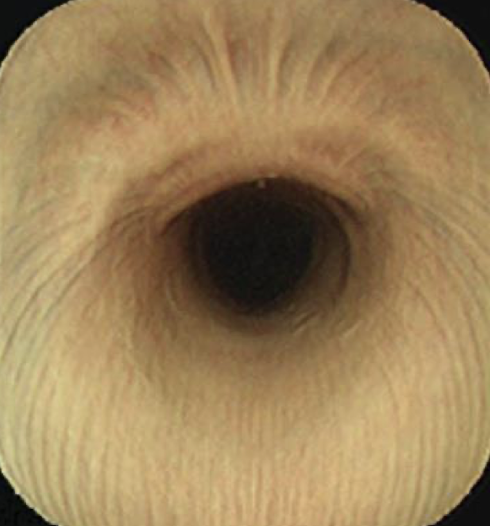

Where do we start the endoscopy procedure?

Start all the way down in the stomach and look cranially

What part of the esophagus is this?

Proximal

Cervical